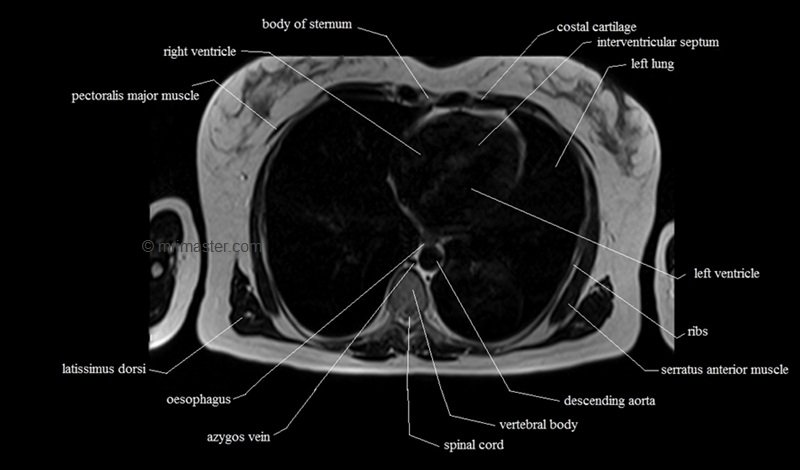

MRI Axial Cross Sectional Anatomy of Chest

This MRI chest (thorax) axial cross sectional anatomy tool is absolutely free to use. Use the mouse scroll wheel to move the images up and down, or alternatively, use the tiny arrows (→) on both sides of the image to navigate through the images. For a more detailed view, double-click the image to view it in full screen, and use the menu in the top right-hand corner to view individual slides or play them in a loop.